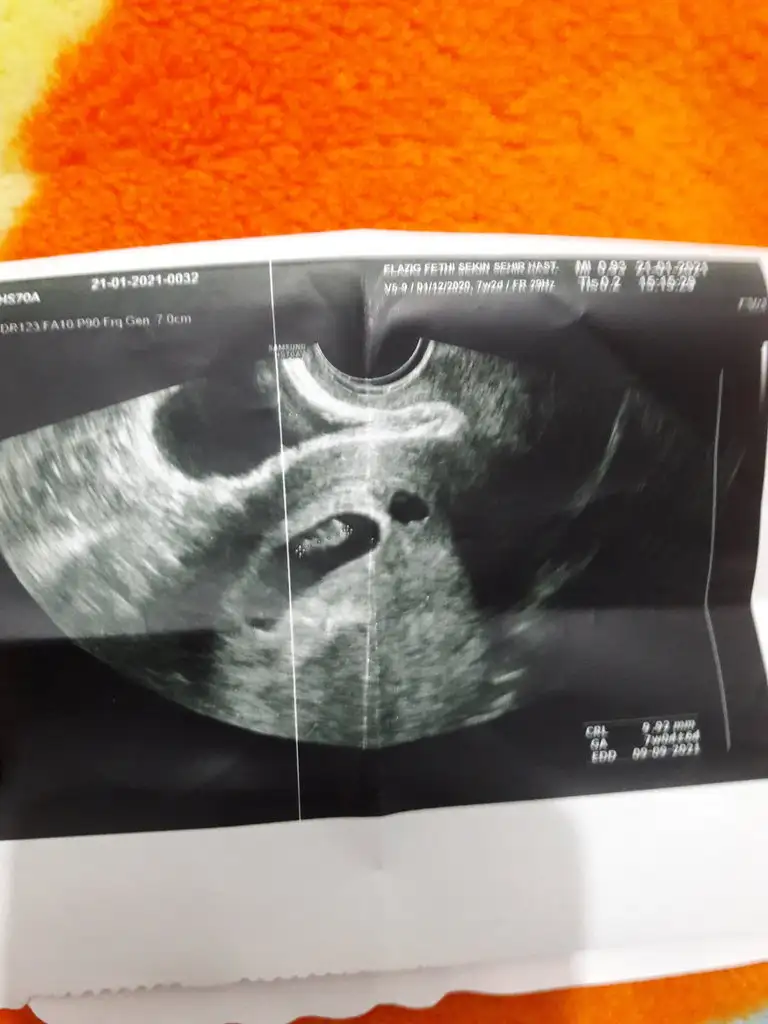

Ramzi teorisine göre cinsiyet tahmini yapacagim ilk ultrasyon resminizi atin bakiyim. Eger cinsiyetiniz belliyse hic söylemeeyin bakalm dogru tahmin edebilecekmiyim daha dogrusu ramzi teorisi hakli cikacak mi?

Kiz diyorum plasenta sagda gibiEki Görüntüle 2783222 Kızlar karından ultrason sizce cinsiyeti ne ?

Kiz diyorum10+4 karindan ultrason.Tahmin yapabilecek varmi cok merak ediyorum.